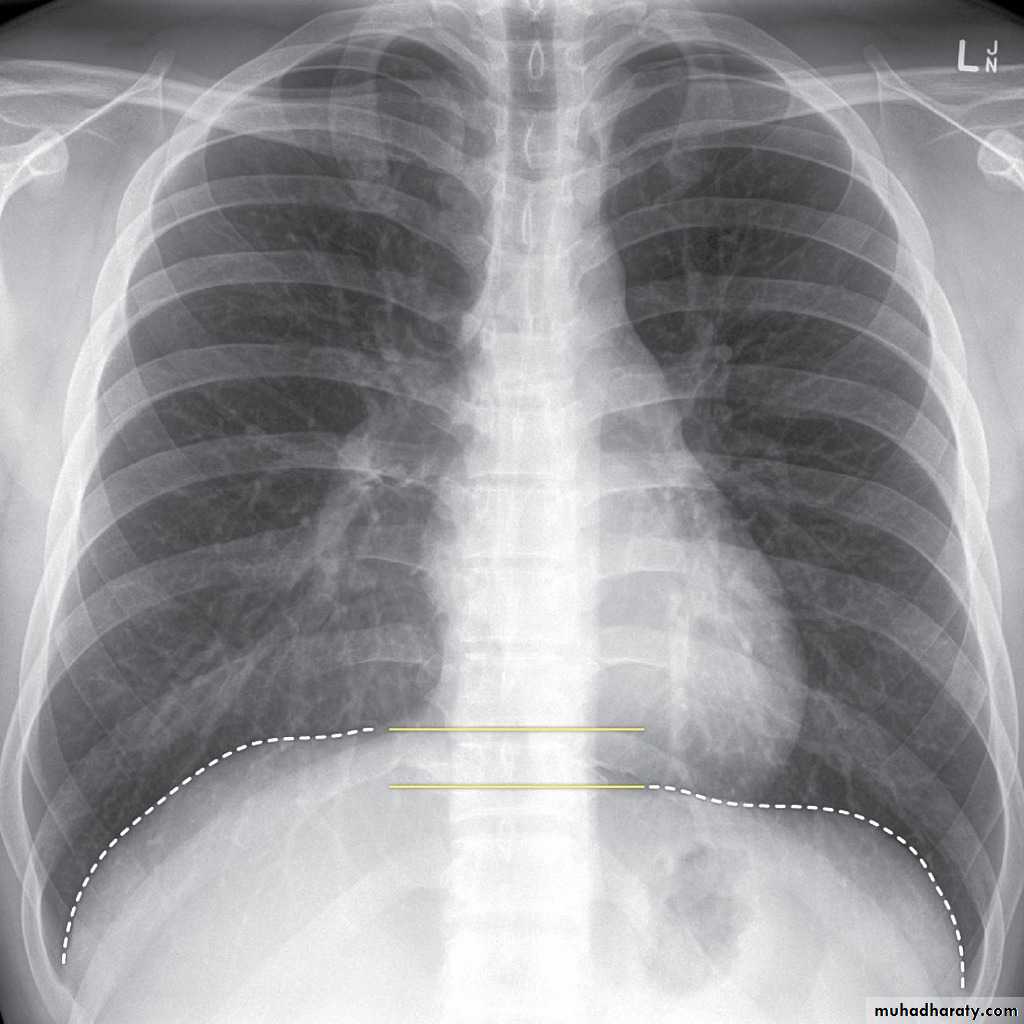

Look carefully on both diaphragmatic cruse costo & cardio phrenic angles

Don't forget to use rib in asses lung Zones

10.normal chest anatomy

11.Radiological lung zone